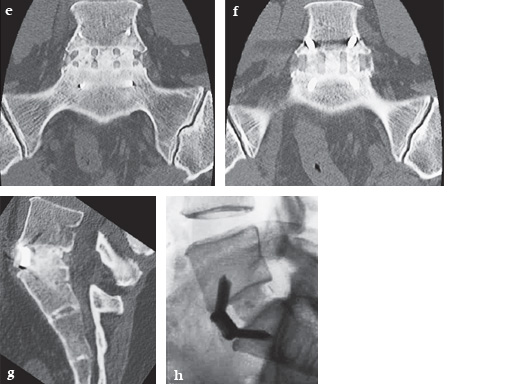

A 37-year-old female (65 kg and 170 cm tall) who suffered from back (L5/S1) and leg pain without neural compression for 2.5 years. She had a full range of conservative treatment and rehabilitation without benefit and reports a significant improvement in symptoms and function following surgery. She has returned to work with minimal restrictions in ongoing activities.

Intraoperative pictures.

Postoperative pictures.